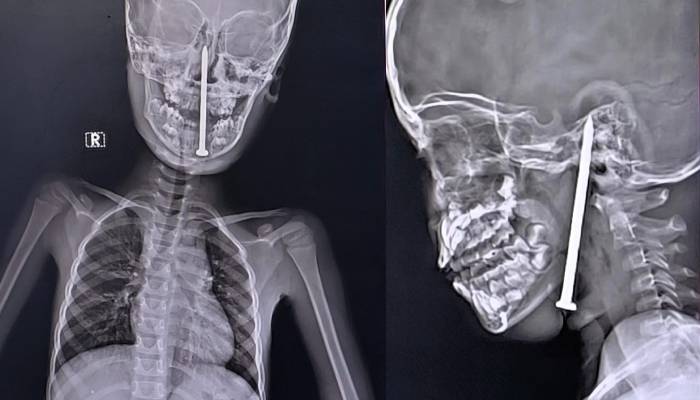

The nail, which was 8cm-long entered through his neck and reached his brain.

After doing MRI and CT scans to find out the exact size and position of the nail, these scans showed that the nail had gone so deep that its tip was touching the boy’s brain.